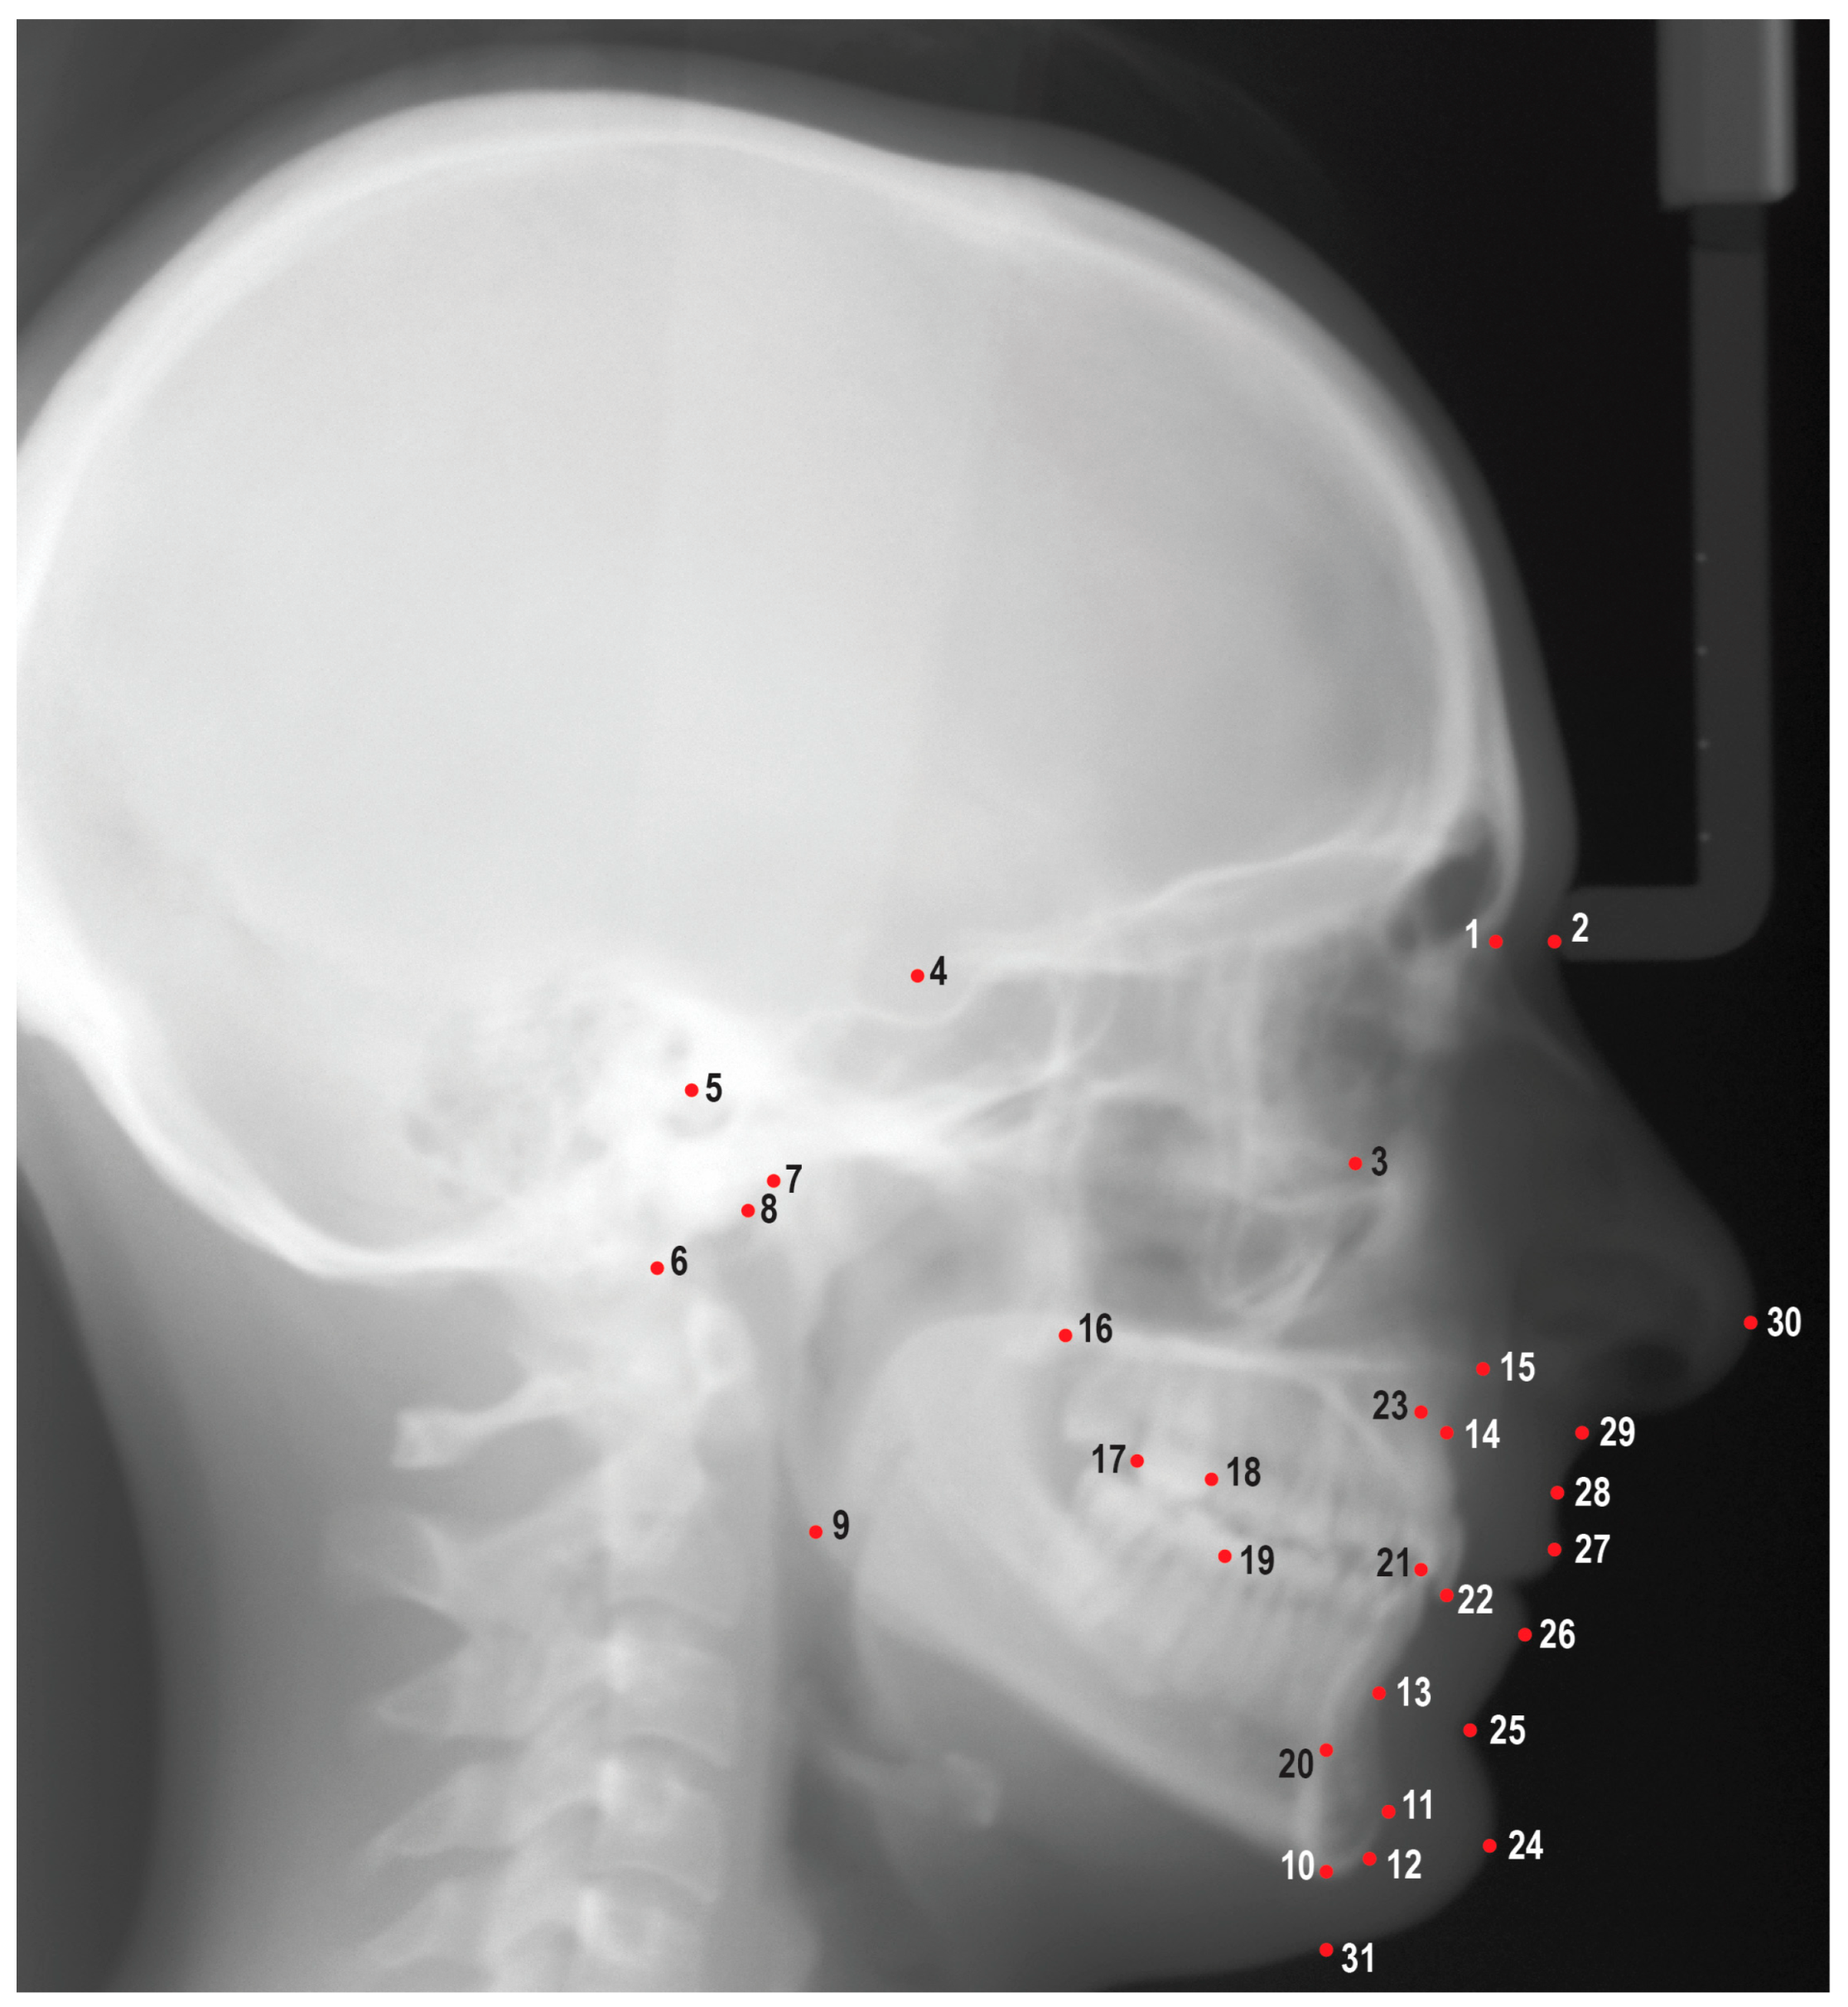

2.2. Data Collection